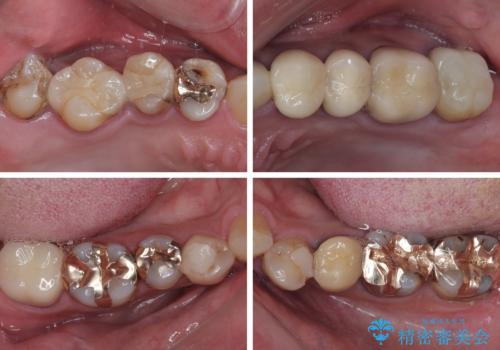

- すぐに欠けてしまう前歯や、むし歯で全顎的に処置された歯を気にして来院された患者様です。

元来むし歯が多く、さらに受け口傾向の咬み合わせを気にしていらっしゃいました。

当初はむし歯処置が必要な歯のみの治療予定でしたが、捻転や咬み合わせを可及的に改善したいとのことで、全顎的にオールセラミッククラウンにて補綴治療を行うこととしました。